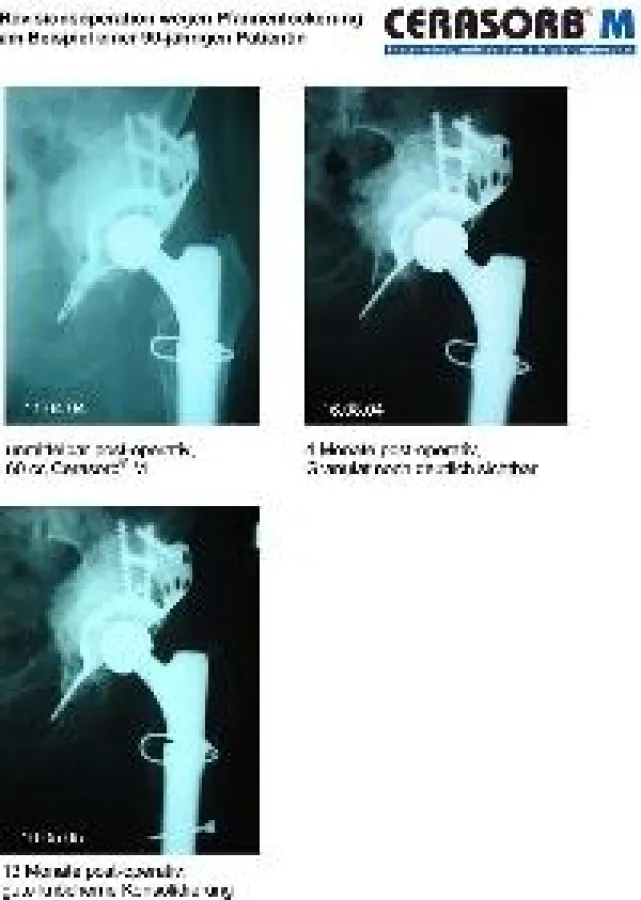

(openPR) Kleinostheim, 8. Mai 2009 - Die curasan AG präsentierte ihre innovativen Medizinprodukte der Dachmarke Cerasorb® für die regenerative orthopädische Medizin (Orthobiologics) auf der Industrieausstellung im Rahmen der 57. Jahrestagung der Vereinigung Süddeutscher Orthopäden e.V. in Baden-Baden. Im Fokus des Interesses stand der Knochenersatzstoff Cerasorb® M, über dessen erfolgreichen Einsatz bei Hüftpfannenrevisionen im Rahmen eines Fachvortrages referiert wurde: Dr. S. Berger aus der Arbeitsgruppe von Prof. C.H. Siebert, Orthopädische Klinik, Annastift, Hannover, berichtete über die positiven Erfahrungen mit dem Einsatz des Knochenersatzstoffes zur Defektauffüllung beim Hüftendoprothesenwechsel. Bei über 30 Patienten im Alter zwischen 60 und 90 Jahren erreichten die Orthopäden mit Cerasorb® M eine gute knöcherne Konsolidierung.

Die Orthopäden setzten Cerasorb® M (ß-Tricalciumphosphat) bei über 30 Operationen ein, in 13 Fällen zusätzlich mit autogenem Knochen. Der anschließende Beobachtungszeitraum betrug mindestens 2 Jahre. In 27 Fällen konnte ein zufriedenstellendes Behandlungsergebnis erzielt werden, obwohl es sich bei vier Patienten um einen septischen Wiedereinbau handelte. "Dies ist offensichtlich in besonderem Maße auf die Phasenreinheit von Cerasorb® M von über 99% zurückzuführen", verdeutlicht Dr. Hübner und führt aus: "Zudem ist eine potentielle Übertragung von Krankheiten, wie sie bei etablierten Produkten aus Human- oder Rinderknochen möglich ist, bei Cerasorb® M ausgeschlossen."

Der Einsatz von Cerasorb® M zur Defektauffüllung bei Hüftendoprothesenwechseln führt somit zu einer hervorragenden knöchernen Konsolidierung. Der neugebildete körpereigene Knochen schafft zudem eine gute Ausgangssituation für weitere eventuell erforderliche Eingriffe. Gerade bei älteren Patienten kann Cerasorb® M allein oder auch in Kombination mit Knochen eingesetzt werden. Cerasorb® M erwies sich altersunabhängig als sinnvolle Alternative zum klassischen Knochenzement für die Defektauffüllung bei Endoprothesenrevisionen.